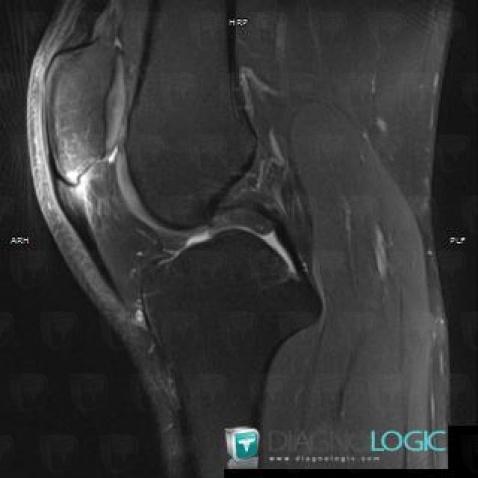

The images below illustrate this case for diagnoses Jumper's knee, for the modalities (MRI)

Jumper's knee, Patellar tendon, MRI

Here is the specific information in the key image above:

- Diagnosis Jumper's knee, Location(s) Patellar tendon, with gamuts